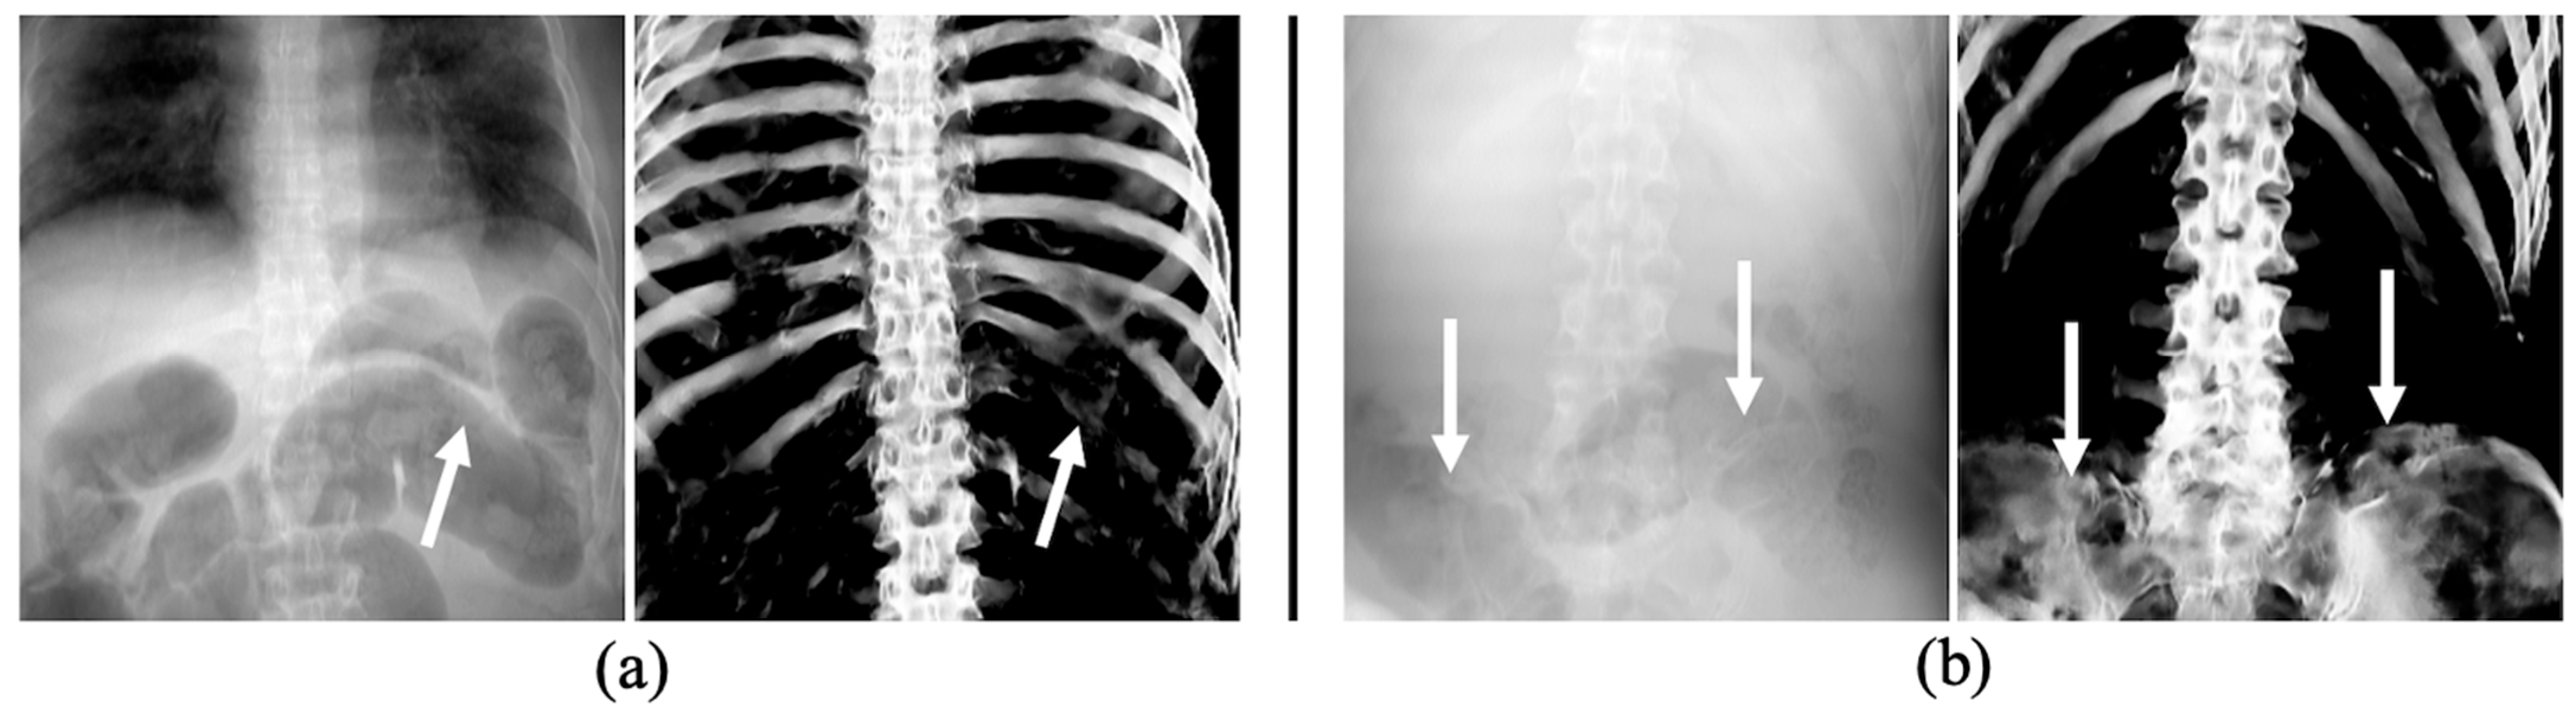

2.3. Pre-Processing: Producing Training Datasets from PMCT Images

3.3. The Performance of Bone Extraction on Real 2D X-ray Images (CXRs)